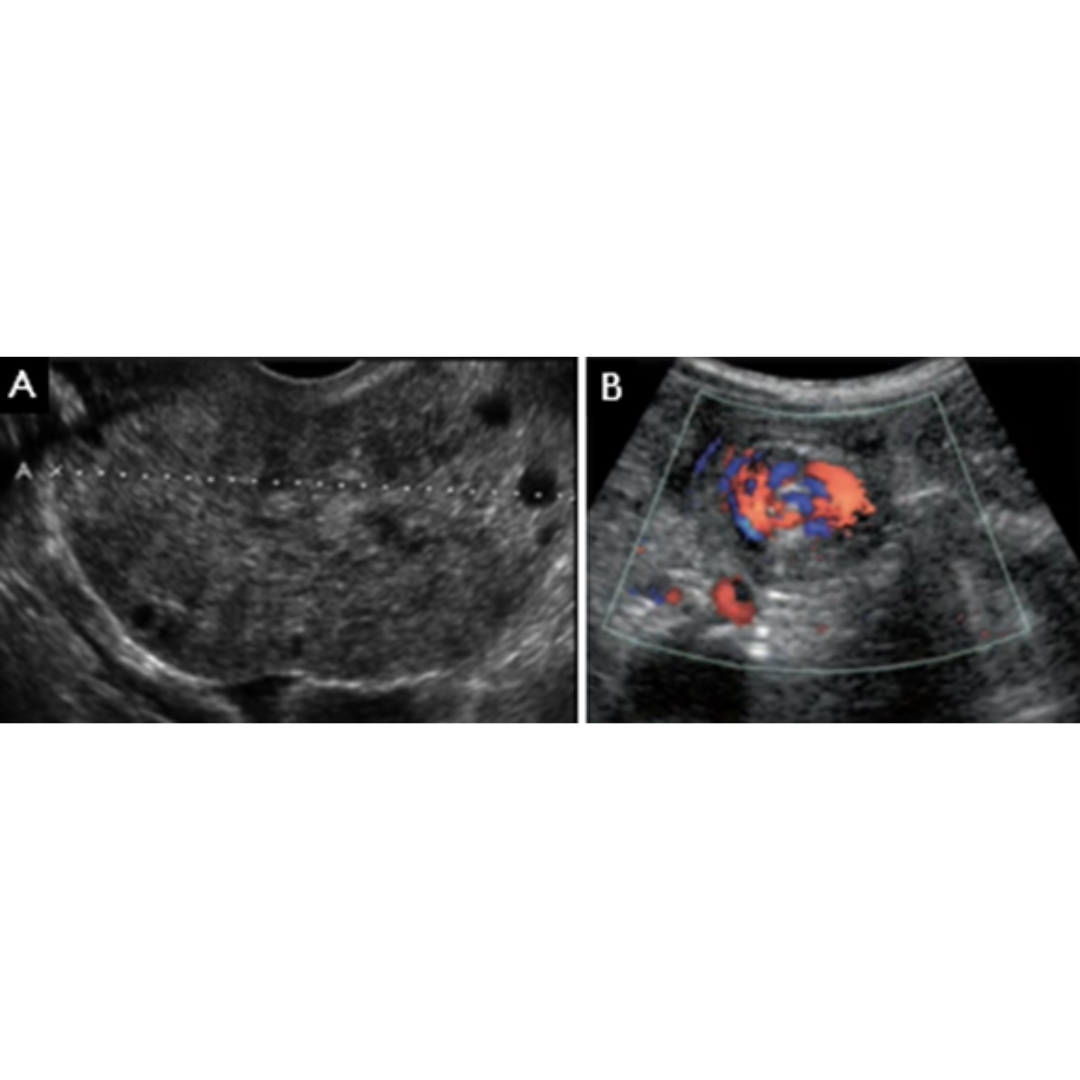

Torsión Ovárica

Causada por anexos muy móviles o frente a la presencia de un quiste o masa anexial preexistente que ejerza peso.

Signos US: Aumento de volumen y tamaño ovárico unilateral (> 4 cm) con folículos desplazados hacia la periferia, estroma ovárico heterogéneo e hiperecogénico, rotación del pedículo ovárico que se evidencia con el “signo del remolino”, presencia de líquido libre en el saco de Douglas.

Figura 7: En (A) se ve ovario aumentado de tamaño con folículos desplazados hacia la periferia, y en (B) el signo del remolino.

Embarazo Ectópico

Implantación del óvulo fecundado fuera de la cavidad uterina, siendo la localización tubárica la más frecuente.

Signos US: saco gestacional fuera del útero con embrión en su interior, masa heterogénea tubárica (signo del anillo tubárico), la cual será hipervascular (signo del anillo de fuego).

Figura 8 6tf: (A) masa anexial con el signo del anillo tubárico, y (B) signo del anillo de fuego frente al Doppler color.